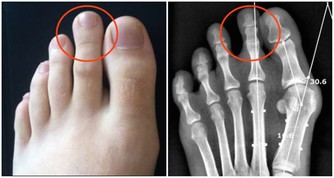

2、痛風石

如果尿酸控制不好,痛風反復發作,大量尿酸結晶沉積在皮下、關節腔內,會形成痛風石,造成關節骨質破壞、畸形。一旦出現痛風石,體內尿酸已經非常高了。